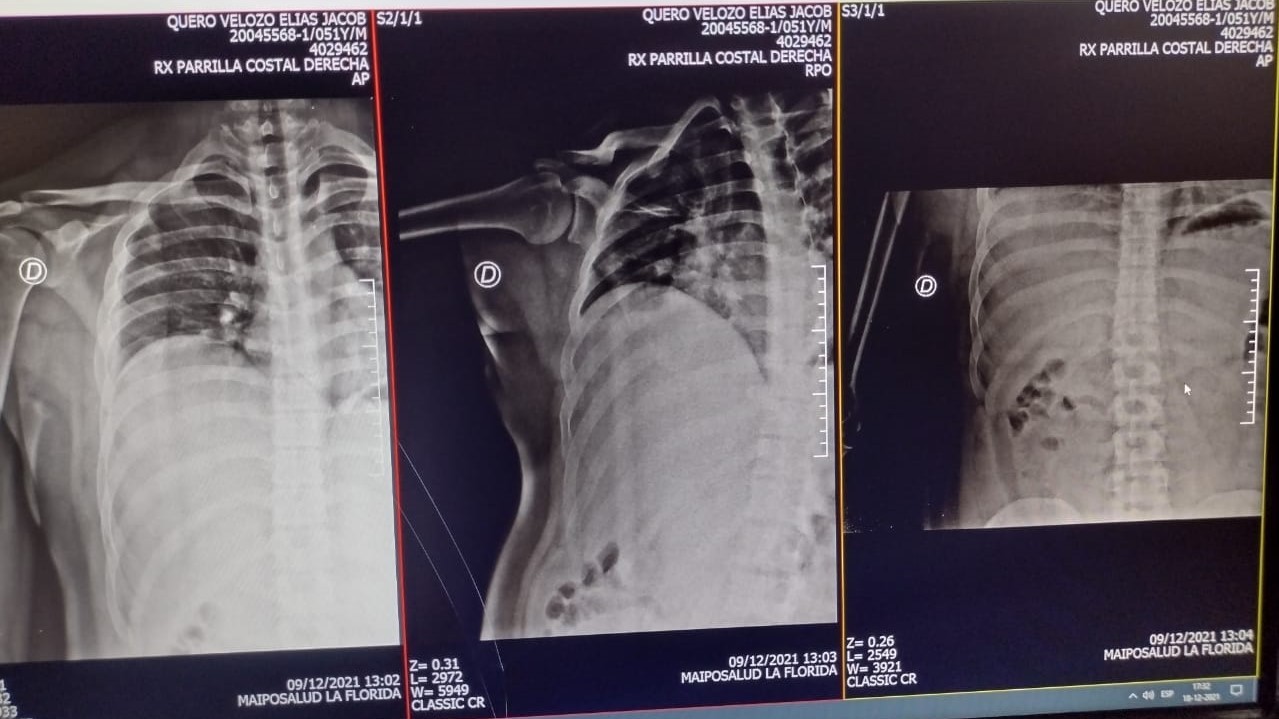

[resumen.cl] El preso político del Estallido Social, Elías Quero denuncia que fue brutalmente golpeado por gendarmes de la cárcel de Puente Alto, especialmente uno que llaman "El Nazi". Elías permanceció más de 1 año en prisión preventiva, tras ser detenido en noviembre de 2020 en una protesta cerca de la estación del Metro Protectora de la Infancia. Este miércoles 1 de diciembre se le modificó la medida cautelar a arresto domiciliario total. El joven de 23 años está imputado por porte de artefacto incendiario. Una acusación sobre la cual su familia ha denunciado que "fue cargado" y que además de las declaraciones de Carabineros, no existen pruebas en su contra. Luego de salir de la cárcel, el joven denunció que el 28 de noviembre fue brutalmente golpeado por funcionarios de Gendarmería con un fierro envuelto en huincha aisladora. Elías difundió los resultados de exámenes realizados el 14 de diciembre, donde se constata que presenta una costilla rota y hemorragia interna.     Como consigna el medio La Voz de los que Sobran uno de los gendarmes que participó en la agresión es conocido adentro de la Cárcel de Puente Alto por el apodo de "El Nazi".